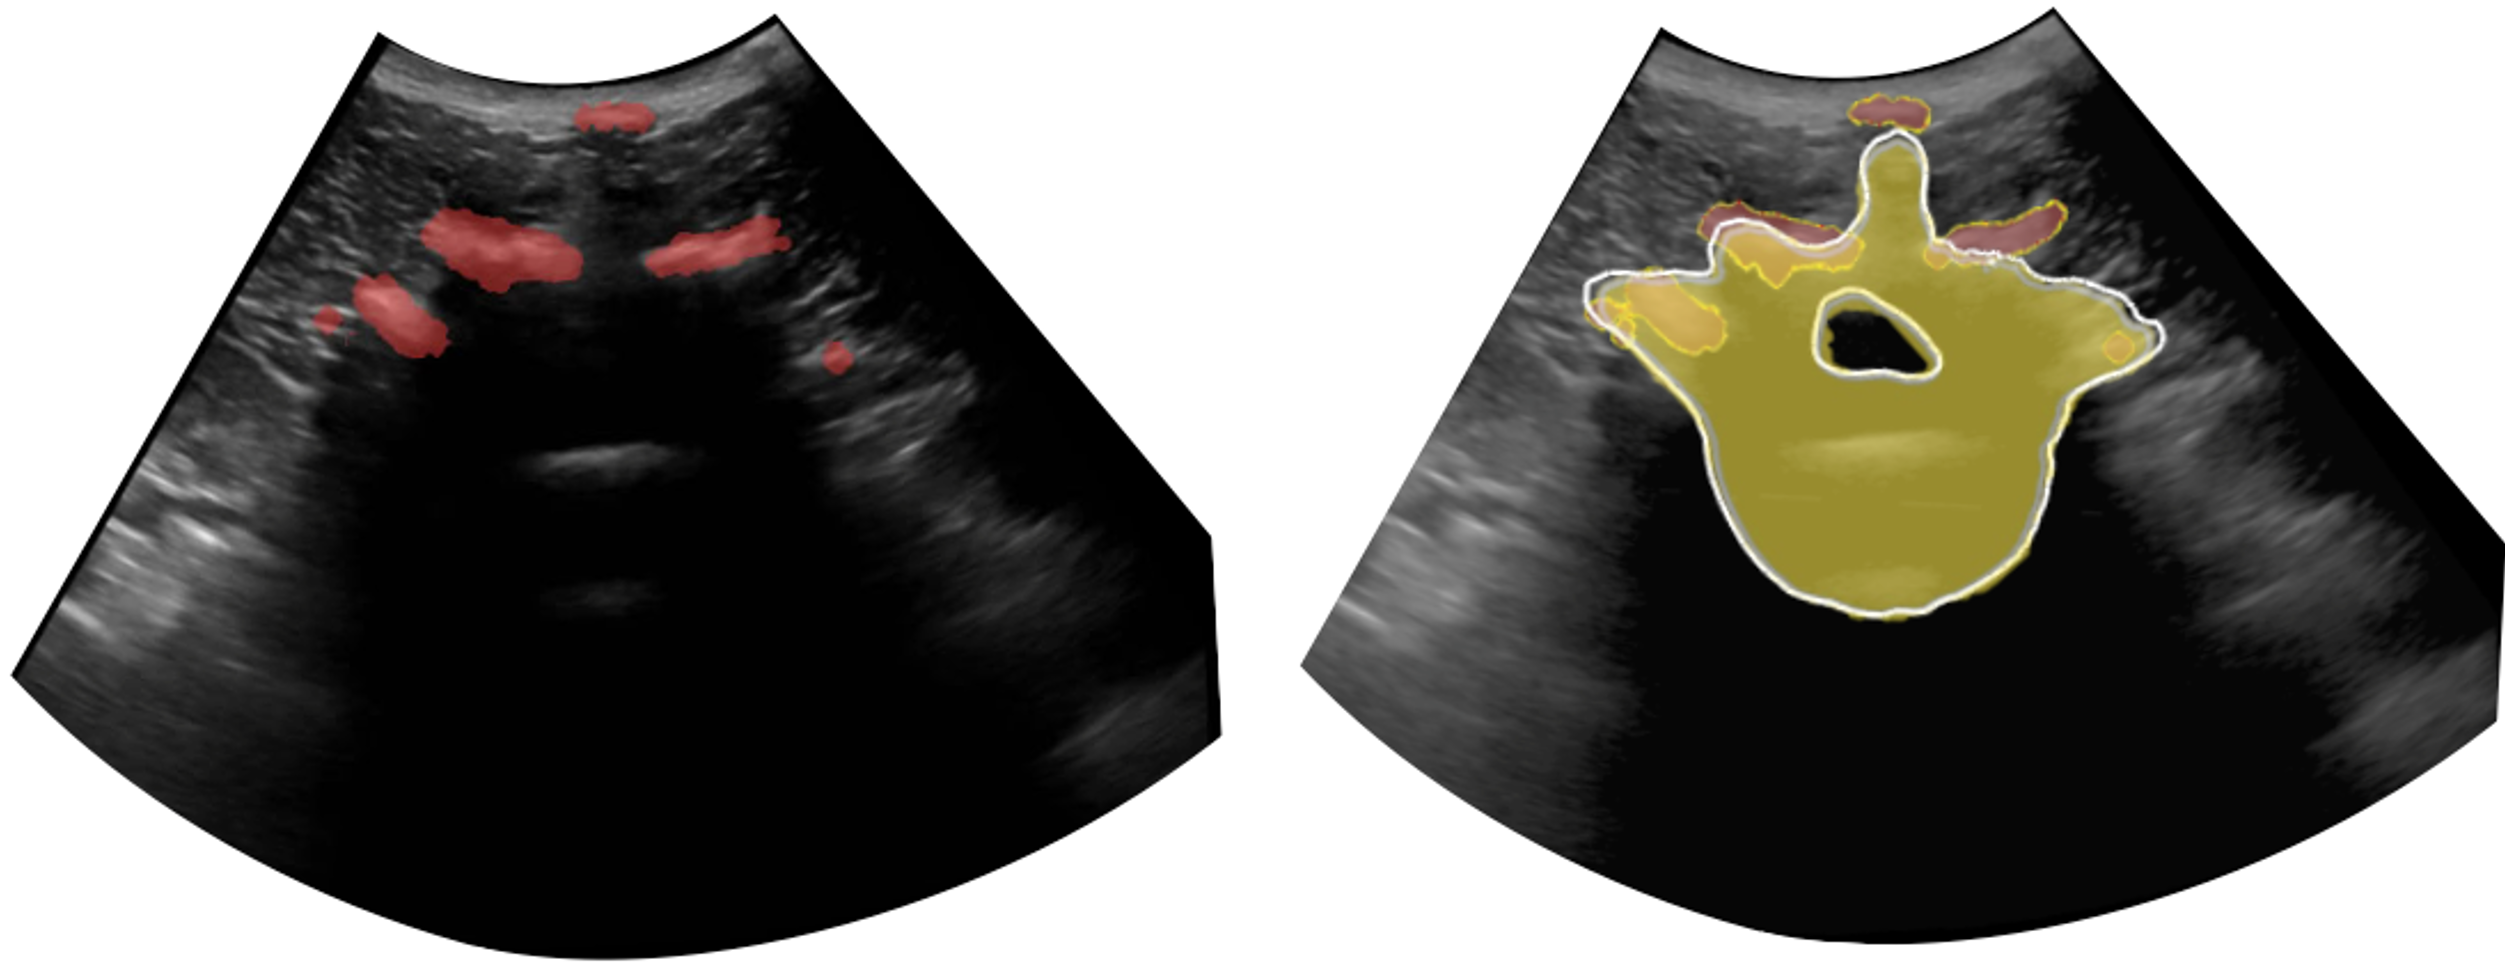

Refer to caption

Figure 5: Qualitative results of our proposed robotic imaging system are shown on the volunteer data. On the left, the live B-mode image is displayed, while on the right, the overlaid completed shape.

We acquire robotic ultrasound scans of a volunteer using the linear scanning approach, followed by manual segmentation. Since no ground truth is available (e.g. from a pre-operatice scan), we present the qualitative results in Figures 4 and 5. We observe that the lateral processes in the predicted completion align well with the input, but discrepancies exist in the spinous processes. Vertebral bodies match the expected size, which can be estimated from the dimensions of the vertebral arches individually. Furthermore, as segmentation of vertebrae in ultrasound is a challenging task, errors in the segmentation can additionally contribute to inconsistencies in the completion results. However, using our proposed robotic ultrasound imaging acquisition system on a volunteer provides with realistic shape completion. These preliminary results indicate the potential of our pipeline to be integrated in spinal ultrasound interventions. Additionally, within a clinical scenario, combining 3D visualization as shown in Figure 4 with slice-by-slice analysis depicted in Figure 5 can reduce the cognitive burden on clinicians, eliminating the need for mental reconstruction of 3D anatomy. Together with 3D visualization of the spine, it can serve as a reference for visualizing critical structures such as nerves and may prove useful in the planning phase.